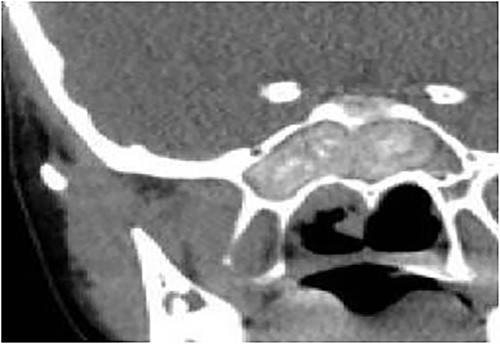

A 13-year-old male presented with progressive right-sided nasal obstruction followed by slowly progressive right eye proptosis noticed by parents for 1 year duration. CT scan of the paranasal sinuses (Fig. 2) confirmed the diagnosis of AFS. The child underwent FESS and received medical treatments post-operatively. The patient remained symptom-free for 4 years follow-up.

Axial CT paranasal sinuses shows the right ethmoid and sphenoid sinuses with complete obliteration and hyperdense (metallic) contents. It is associated with expansion of the ethmoid sinuses and lateral displacement of the right lamina papyracea causing right eye proptosis.